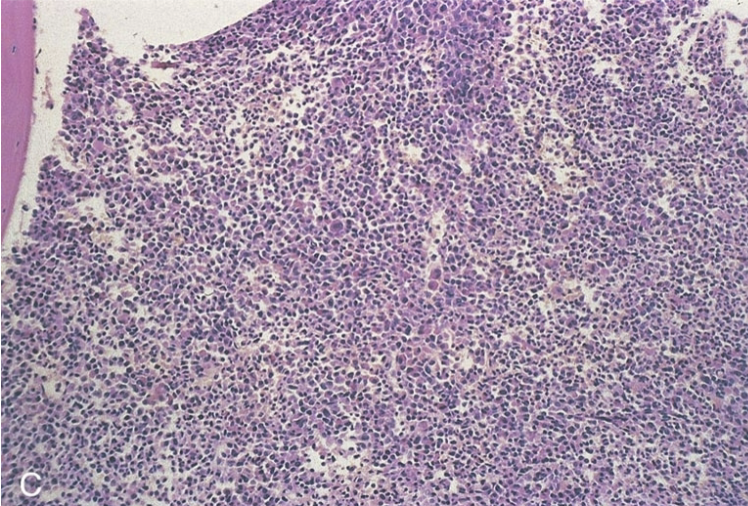

<p>classify the cellularity. include ratio.</p>

classify the cellularity. include ratio.

normal; 1:1

hypercellular; 10:1

hypocellular; 1:10